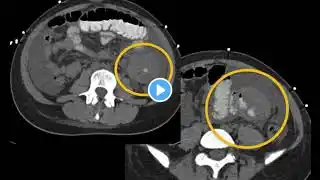

MDCT Evaluation of Gastric Malignancies: Adenocarcinoma, GIST & Beyond Part 2